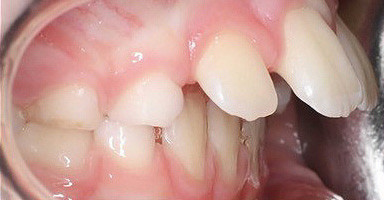

Klinisches Fallbeispiel 1 (Abb. 1a–u)

Neunjähriger Patient mit deutlich vergrößertem Overjet aufgrund eines Distalbisses in Kombination mit einer Protrusion der Oberkieferfront. Habits bzw. myofunktionelle Aspekte wurden adressiert. Die Behandlung erfolgte mit einem Invisalign-Schienensatz (56 Aligner) mit Precsion Wings im Rahmen einer Frühbehandlung zur Prophylaxe eines Frontzahntraumas.